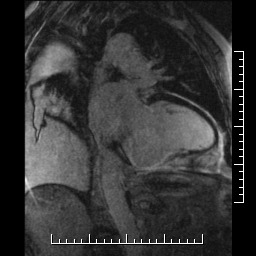

ANEURYSMA A PSEUDOANEURYSMA LEVÉ KOMORY SRDEČNÍ – DIFERENCIÁLNÍ DIAGNOSTIKA POMOCÍ MAGNETICKÉ REZONANCE DOPLNĚNÁ KAZUISTIKAMI

Diferenciální diagnostika aneurysmatu a pseudoaneurysmatu levé komory srdeční je stále obtížná. Aneurysma je definováno jako vyklenutí stěny komory deformující v diastole její typický tvar. Vzniká v důsledku přeměny stěny komory v jizvu a následným působením nitrokomorového tlaku. Oproti tomu pseudoaneurysma vzniká jako postupná ruptura stěny levé komory krytá přilehlým perikardem. Klinický důsledek rozlišení obou stavů je obrovský, protože pseudoaneurysma je vzhledem ke svému riziku ruptury indikací k operačnímu řešení. V primární diagnostice je dnes stále ještě rychlou a dostupnou metodou echokardiografie, avšak vzhledem ke špatné přehlednosti zejména v oblasti spodní a zadní stěny levé komory, kde je pseudoaneurysma nejčastěji lokalizováno, je dnes často využívanou zobrazovací metodou magnetická rezonance. Jde o neinvazivní zobrazovací vyšetření, bez radiační zátěže, s vysokou rozlišovací schopností. V rámci jednoho sezení lze provést vyšetření kinetické, morfologické i postkontrastní (first-pass, late-enhancement). Po podání kontrastní látky se u pseudoaneurysmatu objevuje pozdní sycení perikardu, jehož intenzita signálu je stejná nebo větší než u myokardiální jizvy. Na rozdíl od toho u aneurysmatu je pozdní sycení perikardu vzácné.

Uvádíme 5 krátkých kazuistik (aneurysma spodní stěny, aneurysma hrotu, aneurysma interventrikulárního septa, pseudoaneurysma zadní stěny, stav po resekci pseudoaneurysmatu) včetně obrazové dokumentace, kde vyšetření magnetickou rezonancí přispělo ke stanovení klinické diagnózy a k určení dalšího postupu.